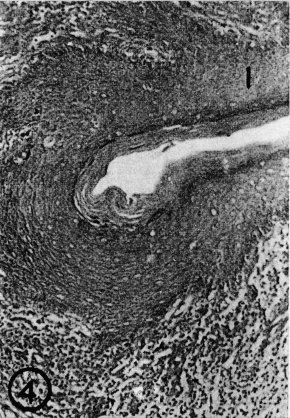

Figure 3

Figure 3: Longitudinal section though adult prepuce showing the free bundles of muscle fibres - Van Giesen's trichrome X 400 (M = Muscle fibre).